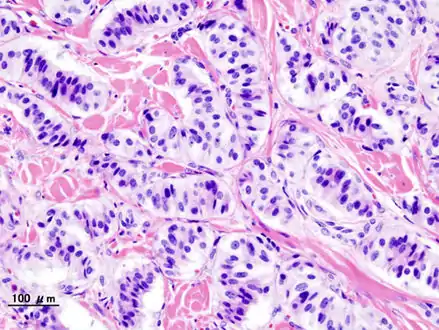

Pathology of pancreatic endocrine tumour (insulinoma). | |

An insulinoma is a tumour of the pancreas that is derived from beta cells and secretes insulin. It is a rare form of a neuroendocrine tumour. Most insulinomas are benign in that they grow exclusively at their origin within the pancreas, but a minority metastasize. Insulinomas are one of the functional pancreatic neuroendocrine tumour (PNET) group ("functional" because it increases production of insulin).[1] In the Medical Subject Headings classification, insulinoma is the only subtype of "islet cell adenoma".[2]